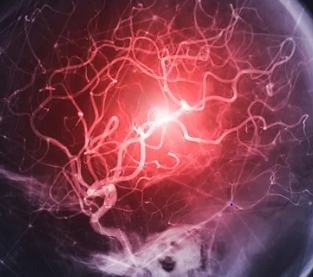

뇌출혈은 뇌 내부의 혈관이 파열되어 혈액이 뇌 조직으로 유출되는 상태를 말합니다. 이는 갑작스러운 두통, 언어 장애, 시력 문제, 신체 일부의 마비 또는 감각 이상과 같은 전조 증상을 동반할 수 있습니다. 뇌출혈의 위험성을 인지하고 적절한 조치를 취하는 것은 중요한데, 이는 뇌 기능에 영구적인 손상을 줄 수 있기 때문입니다. 치료 방법은 뇌출혈의 원인, 위치, 크기에 따라 달라지며, 긴급한 수술이 필요한 경우도 있습니다. 이 서론에서는 뇌출혈의 전조 증상을 인식하는 방법과 가능한 치료 옵션에 대해 자세히 살펴보겠습니다. 이를 통해 독자들이 뇌출혈의 심각성을 이해하고, 필요한 경우 즉시 의학적 도움을 받을 수 있도록 정보를 제공하고자 합니다. 오늘은 뇌출혈의 전조증상 및 치료방법에 대해 알아보겠습니다.

뇌출혈은 뇌 내부의 혈관이 파열되어 혈액이 뇌 조직으로 유출되는 상태를 말합니다. 이는 뇌 기능에 심각한 손상을 줄 수 있는 응급 상황으로, 즉각적인 치료가 필요합니다. 전조 증상으로는 갑작스러운 두통, 언어 장애, 시력 문제, 혼란, 마비 또는 감각 이상 등이 있을 수 있으며, 이러한 증상들은 뇌출혈 발생 전에 나타날 수 있습니다. 치료 방법은 뇌출혈의 원인, 위치, 크기에 따라 달라지며, 일반적으로 수술적 치료와 약물 치료가 병행됩니다. 조기 진단과 적절한 치료가 이루어질 때 예후가 향상될 수 있으므로, 전조 증상을 인지하고 신속히 전문 의료진의 도움을 받는 것이 중요합니다.

뇌출혈, 즉 뇌내 출혈은 뇌 조직 내부에서 발생하는 출혈을 말합니다. 이는 뇌혈관이 파열되어 주변 뇌 조직에 혈액이 새는 상황을 의미하는데, 이로 인해 뇌 조직이 손상되거나 기능이 저하될 수 있습니다. 뇌출혈의 원인은 다양하지만, 주요 원인으로는 고혈압, 뇌동맥류, 혈관 기형, 머리 부상, 혈액 질환, 약물 남용 등이 있습니다.